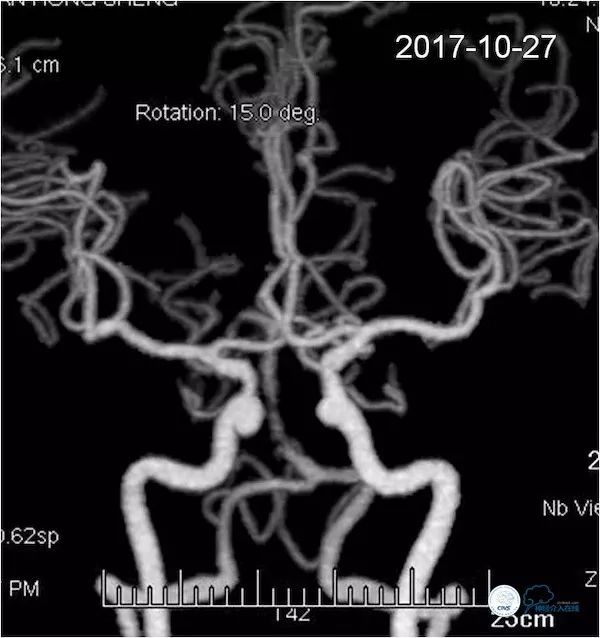

术后查体同前,术后即刻复查头颅CT未见出血。术后复查头颅CTA示基底动脉支架内通畅(图17)。

图17

灌注CT示后循环低灌注区较前改善(图18)。

图18